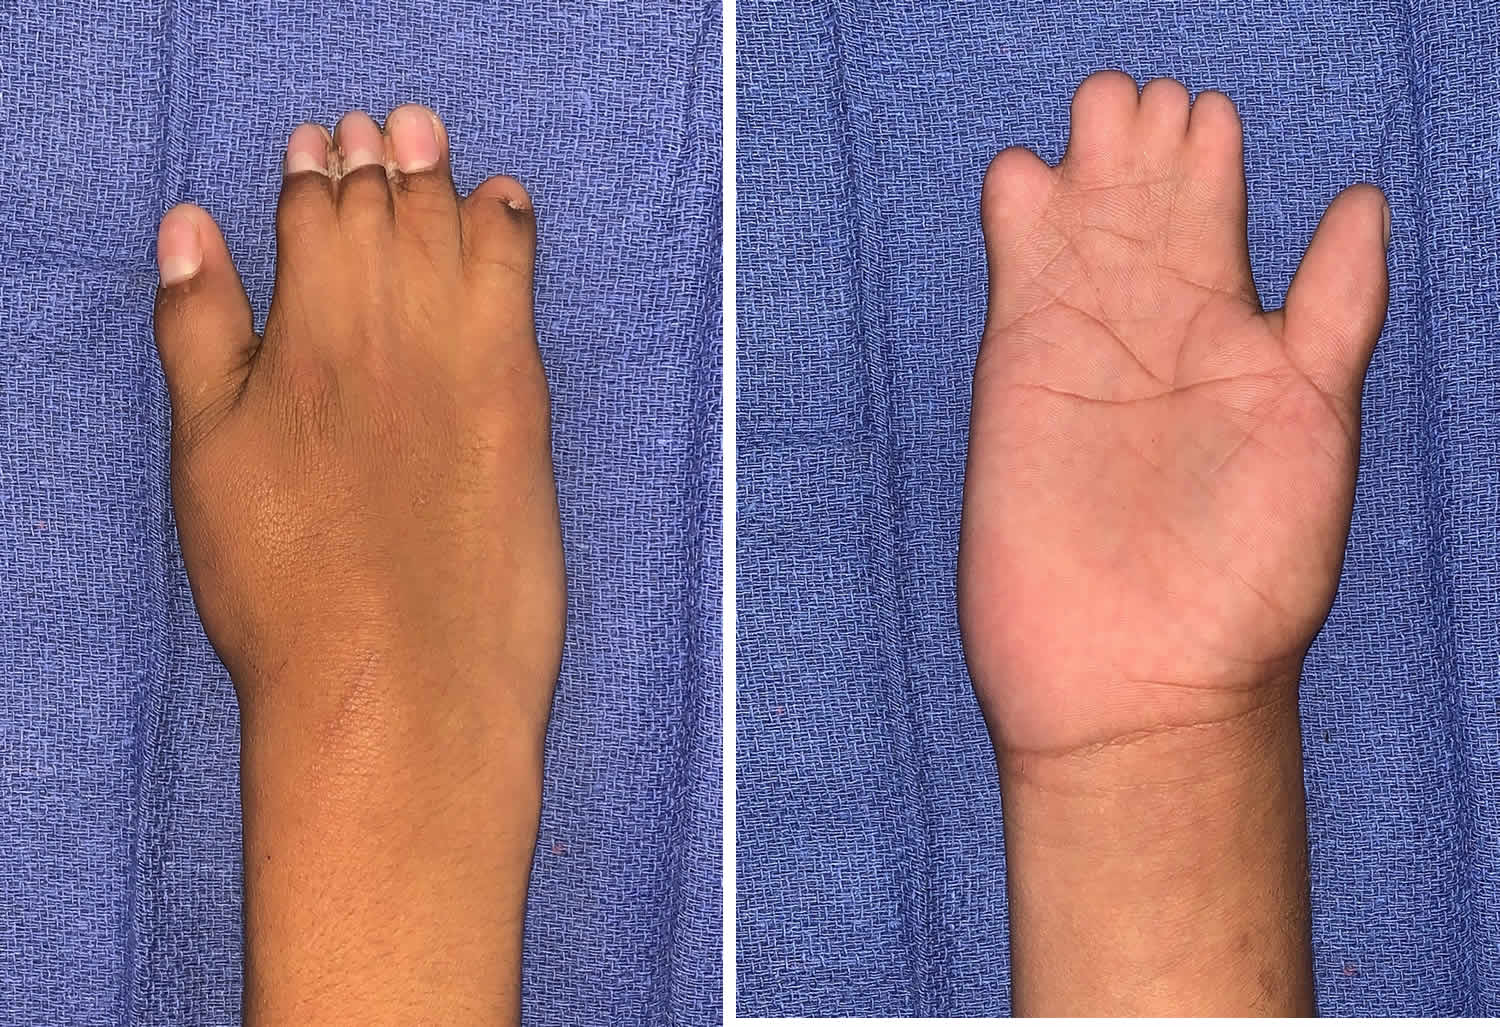

radiologycases.myPoland Syndrome | NEJM

radiologycases.myPoland Syndrome | NEJM

www.nejm.orgpoland syndrome syndrom nejm clinical pectoralis examination dermatology routine noted

www.nejm.orgpoland syndrome syndrom nejm clinical pectoralis examination dermatology routine noted